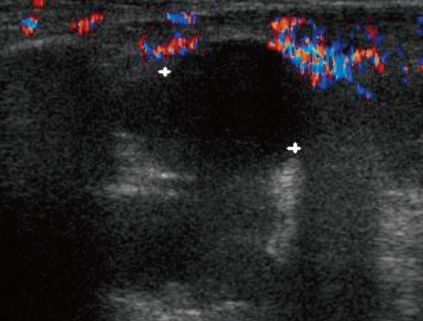

A 13 year-old boy presented with fever and not swollen discomfort of the right elbow without swelling and tenderness. Four months previously, he had been diagnosed to have Ewing sarcoma of the right ilium and had undergone five cycles of preoperative chemotherapy. He had contracted a C. tropicalis urinary tract infection during a febrile neutropenia episode after chemotherapy, which was treated with itraconazole and broad spectrum antibiotics for 7 days. No growth was reported in the last urine culture after itraconazole treatment. Recently, he had been on preoperative chemotherapy (vincristine, ifosfamide, doxorubicin, and etoposide), which he had completed 9 days prior to presentation.At presentation, his body temperature was 37.5℃, pulse rate 120 per minute, respiration rate 20 per minute, and blood pressure 130/70 mmHg. physical examination revealed a slight throat infection, but no sinus tenderness, nor tonsilar nor lymph node enlargement. Heart and lung sounds were normal, liver and spleen were non-palpable, and no edema or pain was found in the lower extremities. He complained of discomfort of the right elbow. Laboratory tests revealed pancytopenia, and complete blood count findings were leukocytes 160/mm3, absolute neutrophil count 40/mm3, hemoglobin 9.4 g/dL, and platelet count 8,000/mm3. Broad-spectrum antibiotics (piperacilin/tazobactam and isepacin) were immediately administered after obtaining blood and urine for culture studies.After two days of antibiotic treatment, mild tenderness and swelling (without heating sensation) were detected on the right elbow. A simple radiograph obtained on the 3rd hospital day revealed soft tissue swelling with a positive fat pad sign (Fig. 1). Ultrasonography on the 4th hospital day showed soft tissue edema and articular effusion, and subsequently, 15 mL of yellowish fluid was aspirated from the joint and cultured (Fig. 2). A three phase bone scan (Fig. 3) performed on the 6th hospital day for the differential diagnosis of tumor metastasis and infection showed a limited region of uptake on the right elbow, suggesting the possibility of arthritis.The symptoms and signs of arthritis aggravated despite a 10-day course of broad-spectrum antibiotics. On the 11th hospital day, cultures of synovial fluid and tissue demonstrated the presence of C. tropicalis. However, blood and urine culture specimens were negative. Follow-up right upper elbow ultrasonography on the 11th hospital day showed elbow articular space effusion and hypertrophic synovium. Emergent decompression was performed on the same day, and a drain tube was placed in the right elbow articular space. During the operation, 2 mL of a yellowish-red turbid synovial fluid sample was obtained and submitted for culture, which later confirmed the presence of C. tropicalis. In addition, abdominal computed tomography on the same day showed no evidence of hepato-splenic candidiasis.Intraveneous itraconazole 400 mg/day (5 mg/kg/day) was started on the 11th and 12th days. Intravenous itraconazole was decreased to 200 mg/day on the 13th day and then kept at the same dose. Fever, joint swelling, and arthralgia gradually resolved after itraconazole treatment, and after 2 weeks of intravenous itraconazole treatment on the 25th hospital day. Intravenous itraconazole 200 mg/day was substituted for oral itraconazole solution at 200 mg/day.The antifungal treatment was maintained for three months, and from 14 days after treatment commencement the patient had no elbow pain and was without disability. Furthermore, no relapse of the fungal arthritis occurred during oral itraconazole therapy. Simple radiography and a bone scan carried out after 3 months of antifungal treatment showed no abnormal lesion related to septic arthritis, and oral itraconazole was discontinued.